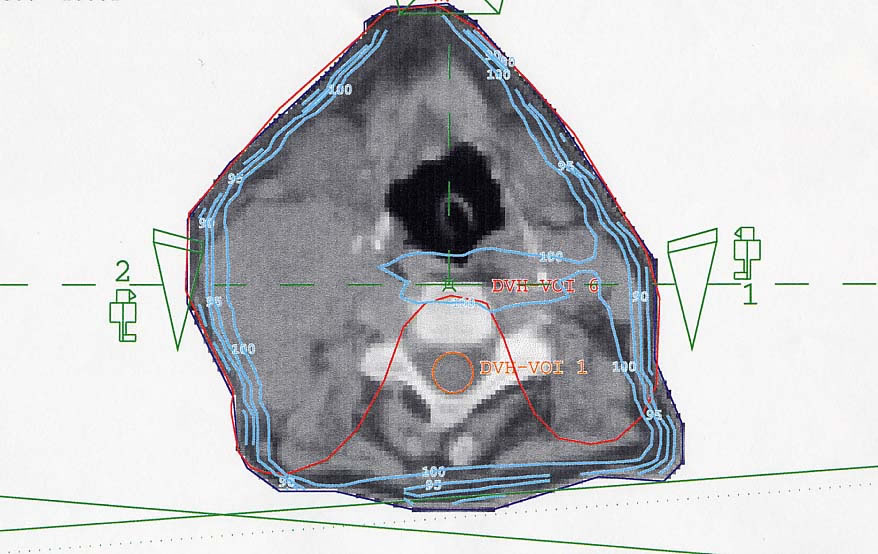

HNO-Karzinome: Bestrahlungsplan